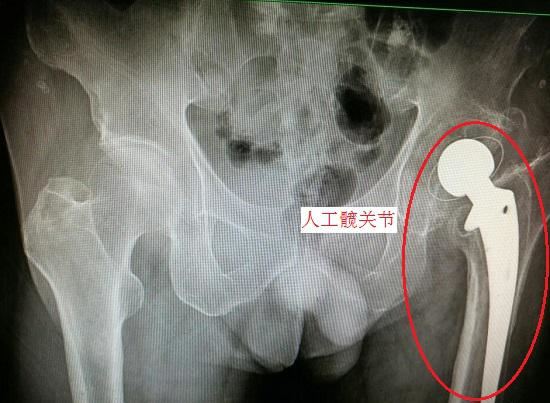

髋关节置换术

股骨颈骨折后的关节置换,需要对股骨头及断裂的股骨颈进行人工假体置换,并在置换后实施长期的康复训练,预后情况与患者伤前髋关节状况、手术技术、术后康复治疗水平、患者配合度等因素高度相关,需要进行较大范围的组织切割和结构改造,对于普通的股骨颈骨折并不适用。股骨颈骨折后髋关节置换术的适应证主要有:1、存在退行性骨关节炎;2、股骨头坏死、缺血;3、髋臼发育不良并引发髋关节炎的;4、类风湿关节炎和强直性关节炎使髋关节受累;5、骨质差的老年患者;6、髋关节发育不良者并引发显著症状的;7、髋关节的持续感染、髋关节肿瘤等髋部病变;8、其他病变且非手术治疗无效者。